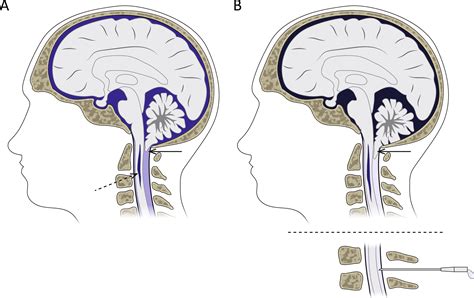

The most common procedure is a posterior fossa decompression. During this surgery, the neurosurgeon removes a small piece of bone at the back of the skull to create more space for the cerebellum. This reduces pressure on the brainstem and restores the normal flow of cerebrospinal fluid. In many cases, the dura mater (the tough membrane covering the brain) is also opened and enlarged with a patch graft to provide additional room.

Managing Hydrocephalus

Because hydrocephalus is a frequent companion to Chiari Malformation Type 2, surgeons often need to address fluid accumulation using a shunt system. A shunt is a flexible tube that diverts excess cerebrospinal fluid from the brain to another part of the body, usually the abdomen, where it can be safely absorbed.